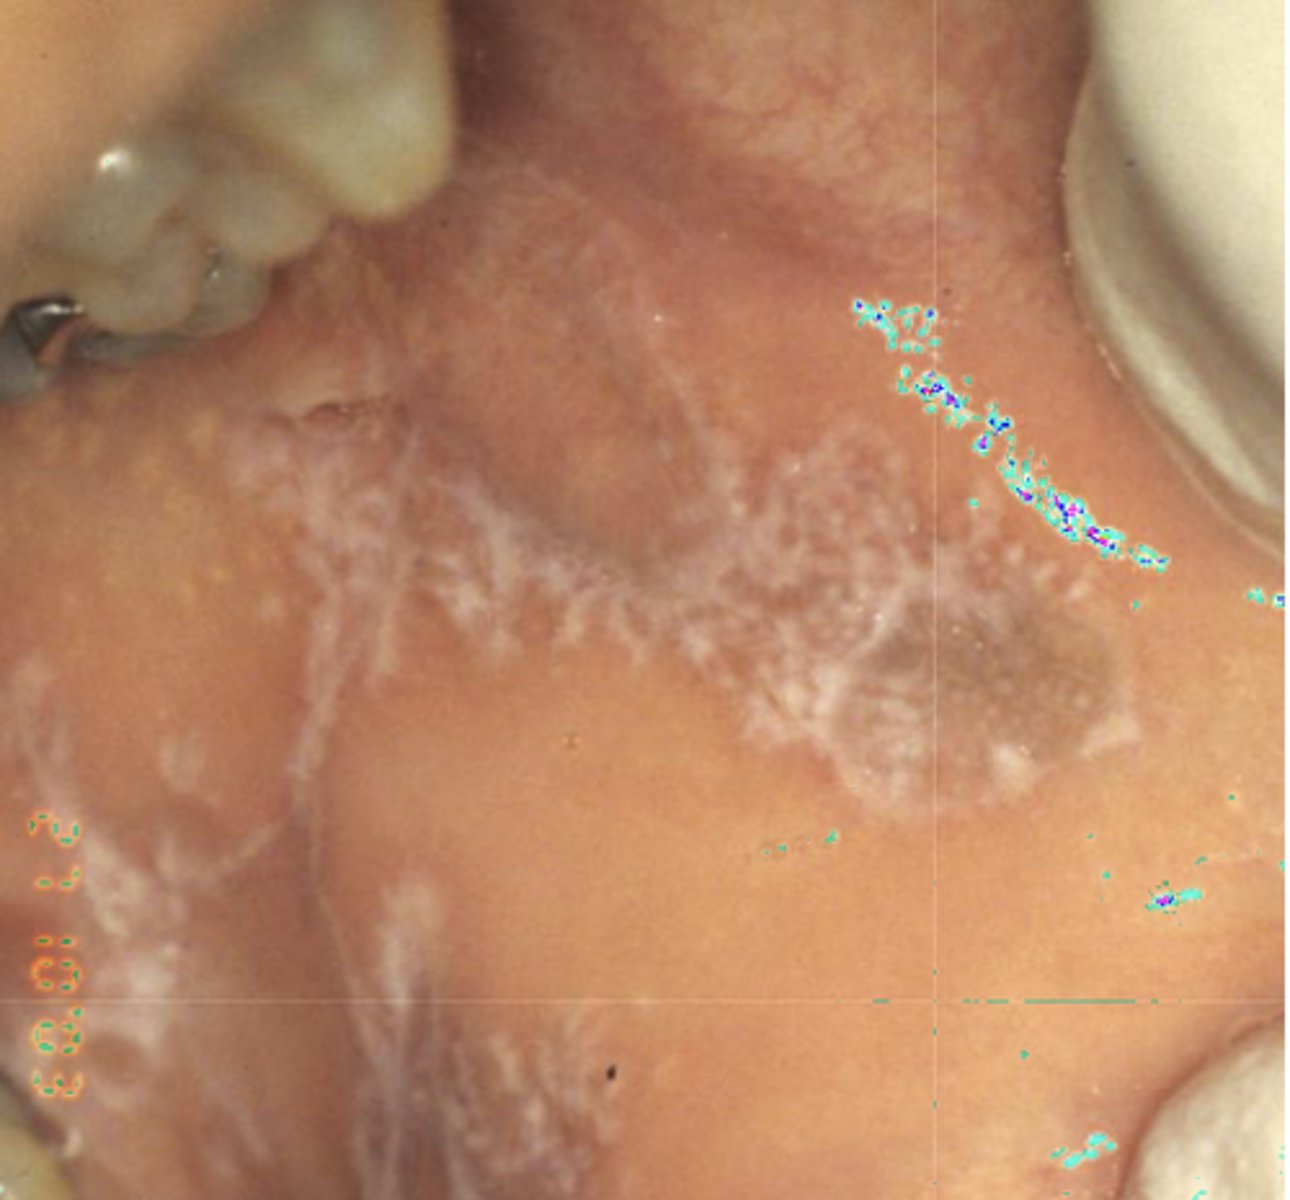

These are histopathologic features of what?

- Pigmented fragments

- Staining of reticulin fibers

- Large fragments surrounded by fibrosis

amalgam tattoos